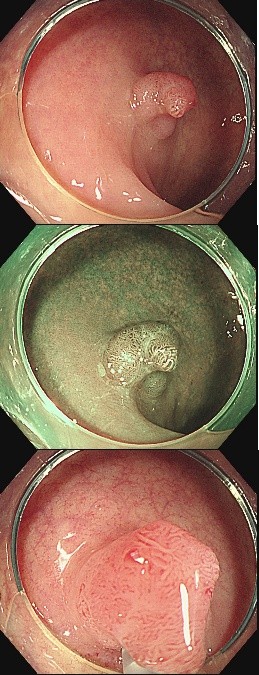

대장내시경을 시행한 58세 남성 환자의 사례입니다.

검사 중 항문에서 12cm 떨어진 부위에서

1cm가량의 용종이 관찰되어 내시경적 점막절제술(EMR)을 시행하였습니다.

하지만, 육안으로는 심각해 보이지 않았던 이 용종의 조직 검사 결과는 놀라웠습니다.

*중등도 분화의 선암(adenocarcinoma)* 으로 진단되었으며,

관상융모선종tubulovillous adenoma에서 발생한 고위험 상태였습니다.